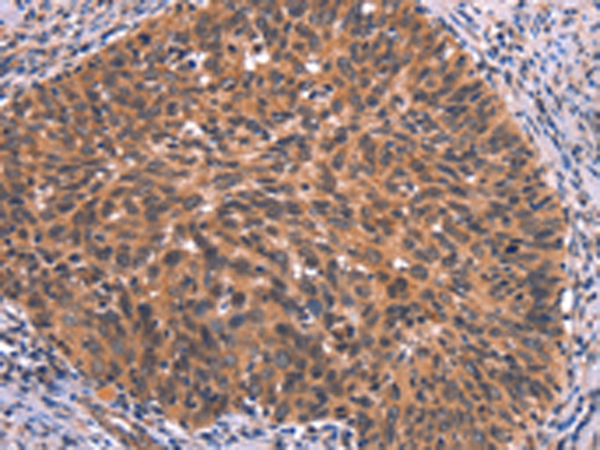

分类: 科研抗体货号: P04879别名: ATOD2应用: IHC反应种属: Human